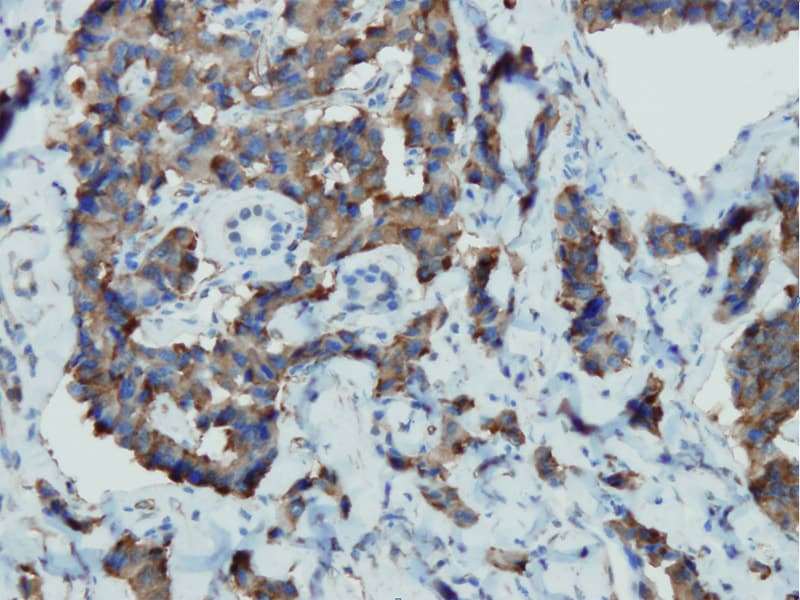

Na mucosa gastrointestinal normal, a CgA está presente em células endócrinas e é a principal proteína da família das graninas expressa em muitos tecidos neuroendócrinos. Estudos imuno-histoquímicos demonstraram uma coloração intensa de CgA em células endócrinas do estômago ao reto, destacando a sua ubiquidade entre as populações de células neuroendócrinas no trato digestivo. A expressão de CgA reflete a presença de grânulos de núcleo denso, que são caraterísticos da diferenciação neuroendócrina. Este atributo biológico sustenta o seu significado diagnóstico: a CgA permite a visualização e identificação de células de linhagem neuroendócrina e tumores em tecidos gastrointestinais que, de outra forma, poderiam ser indistinguíveis na histologia de rotina.

Em patologia gastrointestinal, a imuno-histoquímica para CgA é um marcador estabelecido para a diferenciação neuroendócrina e é rotineiramente incluída em painéis para caraterizar suspeitas de neoplasias neuroendócrinas (NENs). Os tumores neuroendócrinos (NETs) do sistema gastroenteropancreático demonstram frequentemente uma expressão robusta de CgA, o que auxilia na sua distinção de carcinomas não neuroendócrinos. A coloração de CgA é particularmente valiosa porque muitos NETs secretam CgA independentemente de síndromes hormonais, proporcionando sensibilidade na deteção de tumores tanto funcionais como não funcionais. No entanto, os padrões de expressão de CgA podem variar entre os subtipos tumorais: por exemplo, alguns carcinoides retais podem apresentar menor imunorreatividade para CgA, sublinhando a importância da seleção do anticorpo e de painéis de marcadores abrangentes.

Os anticorpos anti-Cromogranina A desenvolvidos para imuno-histoquímica CE/IVD são concebidos para elevada especificidade e reprodutibilidade em cortes de tecido fixados em formalina e embebidos em parafina (FFPE). Estes anticorpos visam epítopos na proteína CgA para visualizar o antigénio intracelular por microscopia ótica num fluxo de trabalho de diagnóstico clínico. Anticorpos de elevada qualidade são rigorosamente validados em tecidos gastrointestinais humanos para garantir uma coloração robusta de células neuroendócrinas que expressam CgA, com background e reatividade cruzada mínimos.